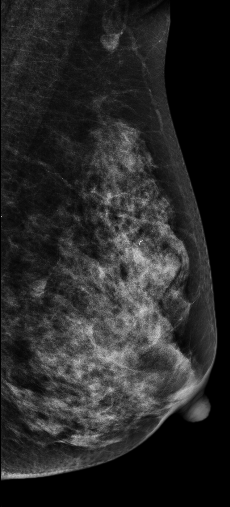

2D图像:

在常规2D图像右乳外上象限隐约见一不规则团块影,部分边界模糊(容易漏掉),边缘可见粗大钙化灶,在V-Preview图像MLO位和CC位上团块显示较模糊,但钙化清晰可见,在3D-slab图像上我们可以清晰见到病灶呈分叶状改变,边缘可见蛋壳样钙化灶,周边见细线样透亮环。从以上细微征象我们可以初步判断是一良性病灶。